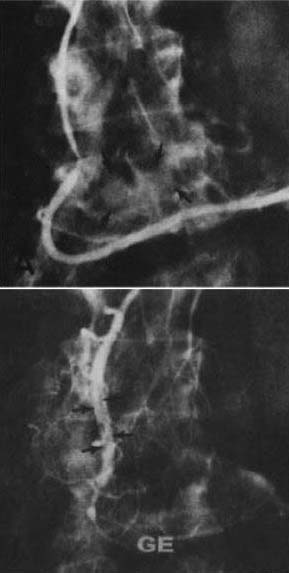

図1.(左)Adamkiewicz動脈を流入動脈とする血管奇形.(右)塞栓術後.病変は消失.

【要旨】 27歳男性,脊髄動静脈奇形.5年前に突然の背部痛,下肢筋力低下.椎弓切除後を行なったが血管病変については手術適応なしとされ,その後症状が再発,進行した.血管造影では,腰動脈からの上行枝とAdamkiewicz動脈からの下行枝,2本流入血管が認められた(図1).まず上行枝に鉛ペレットを注入したが塞栓できず,大腿四頭筋の筋肉片で塞栓した.3日後,下行枝にも同様にまず鉛ペレットを注入したが閉塞せず,筋肉片で完全で閉塞した.術後の血管造影で病変は消失した.患者の症状は徐々に回復し,術前は対麻痺であったが歩行可能となった.

【解説】 画像下治療(IVR)の重要分野のひとつである経カテーテル的血管塞栓術の初の報告例である.脊髄血管奇形の手術治療として全摘は難しく,かえって症状が悪化することが多かった.当時,流入動脈の結紮術が推奨され,少なくとも症状の悪化はないことから,外科的結紮にかえて経カテーテル的塞栓術を試みたものである.塞栓物質には,鉛ペレットと筋肉小片を使用しているが,これ以前にも,主に内頸動脈海綿静脈洞瘻に対して開頭下に金属片,筋肉片,ゼルフォームを塞栓物質として使用することは行なわれていた.1972年に同じく経カテーテル的な脊髄動静脈奇形の塞栓術7例を報告した Doppman,Di Chiroらは,ステンレス片と筋肉片を使用している[8].その後,様々な塞栓物質が開発され試みられるようになった.